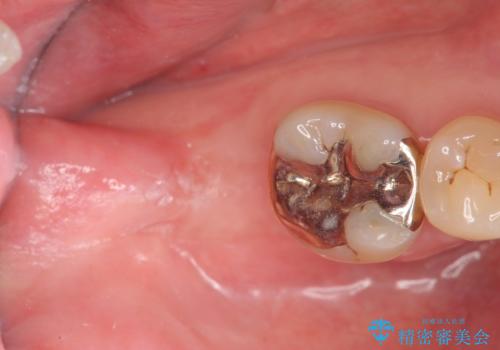

- 右下奥歯がグラグラし、噛めないことの改善を希望され来院されました。

X線写真より根尖付近までの骨吸収を認めます。

抜歯を余儀なくされる状況ですが、将来的にインプラントによる咬合機能回復を希望されたので抜歯と同時に骨補填剤を填入し骨の造成をしたのちのインプラント治療を計画します。